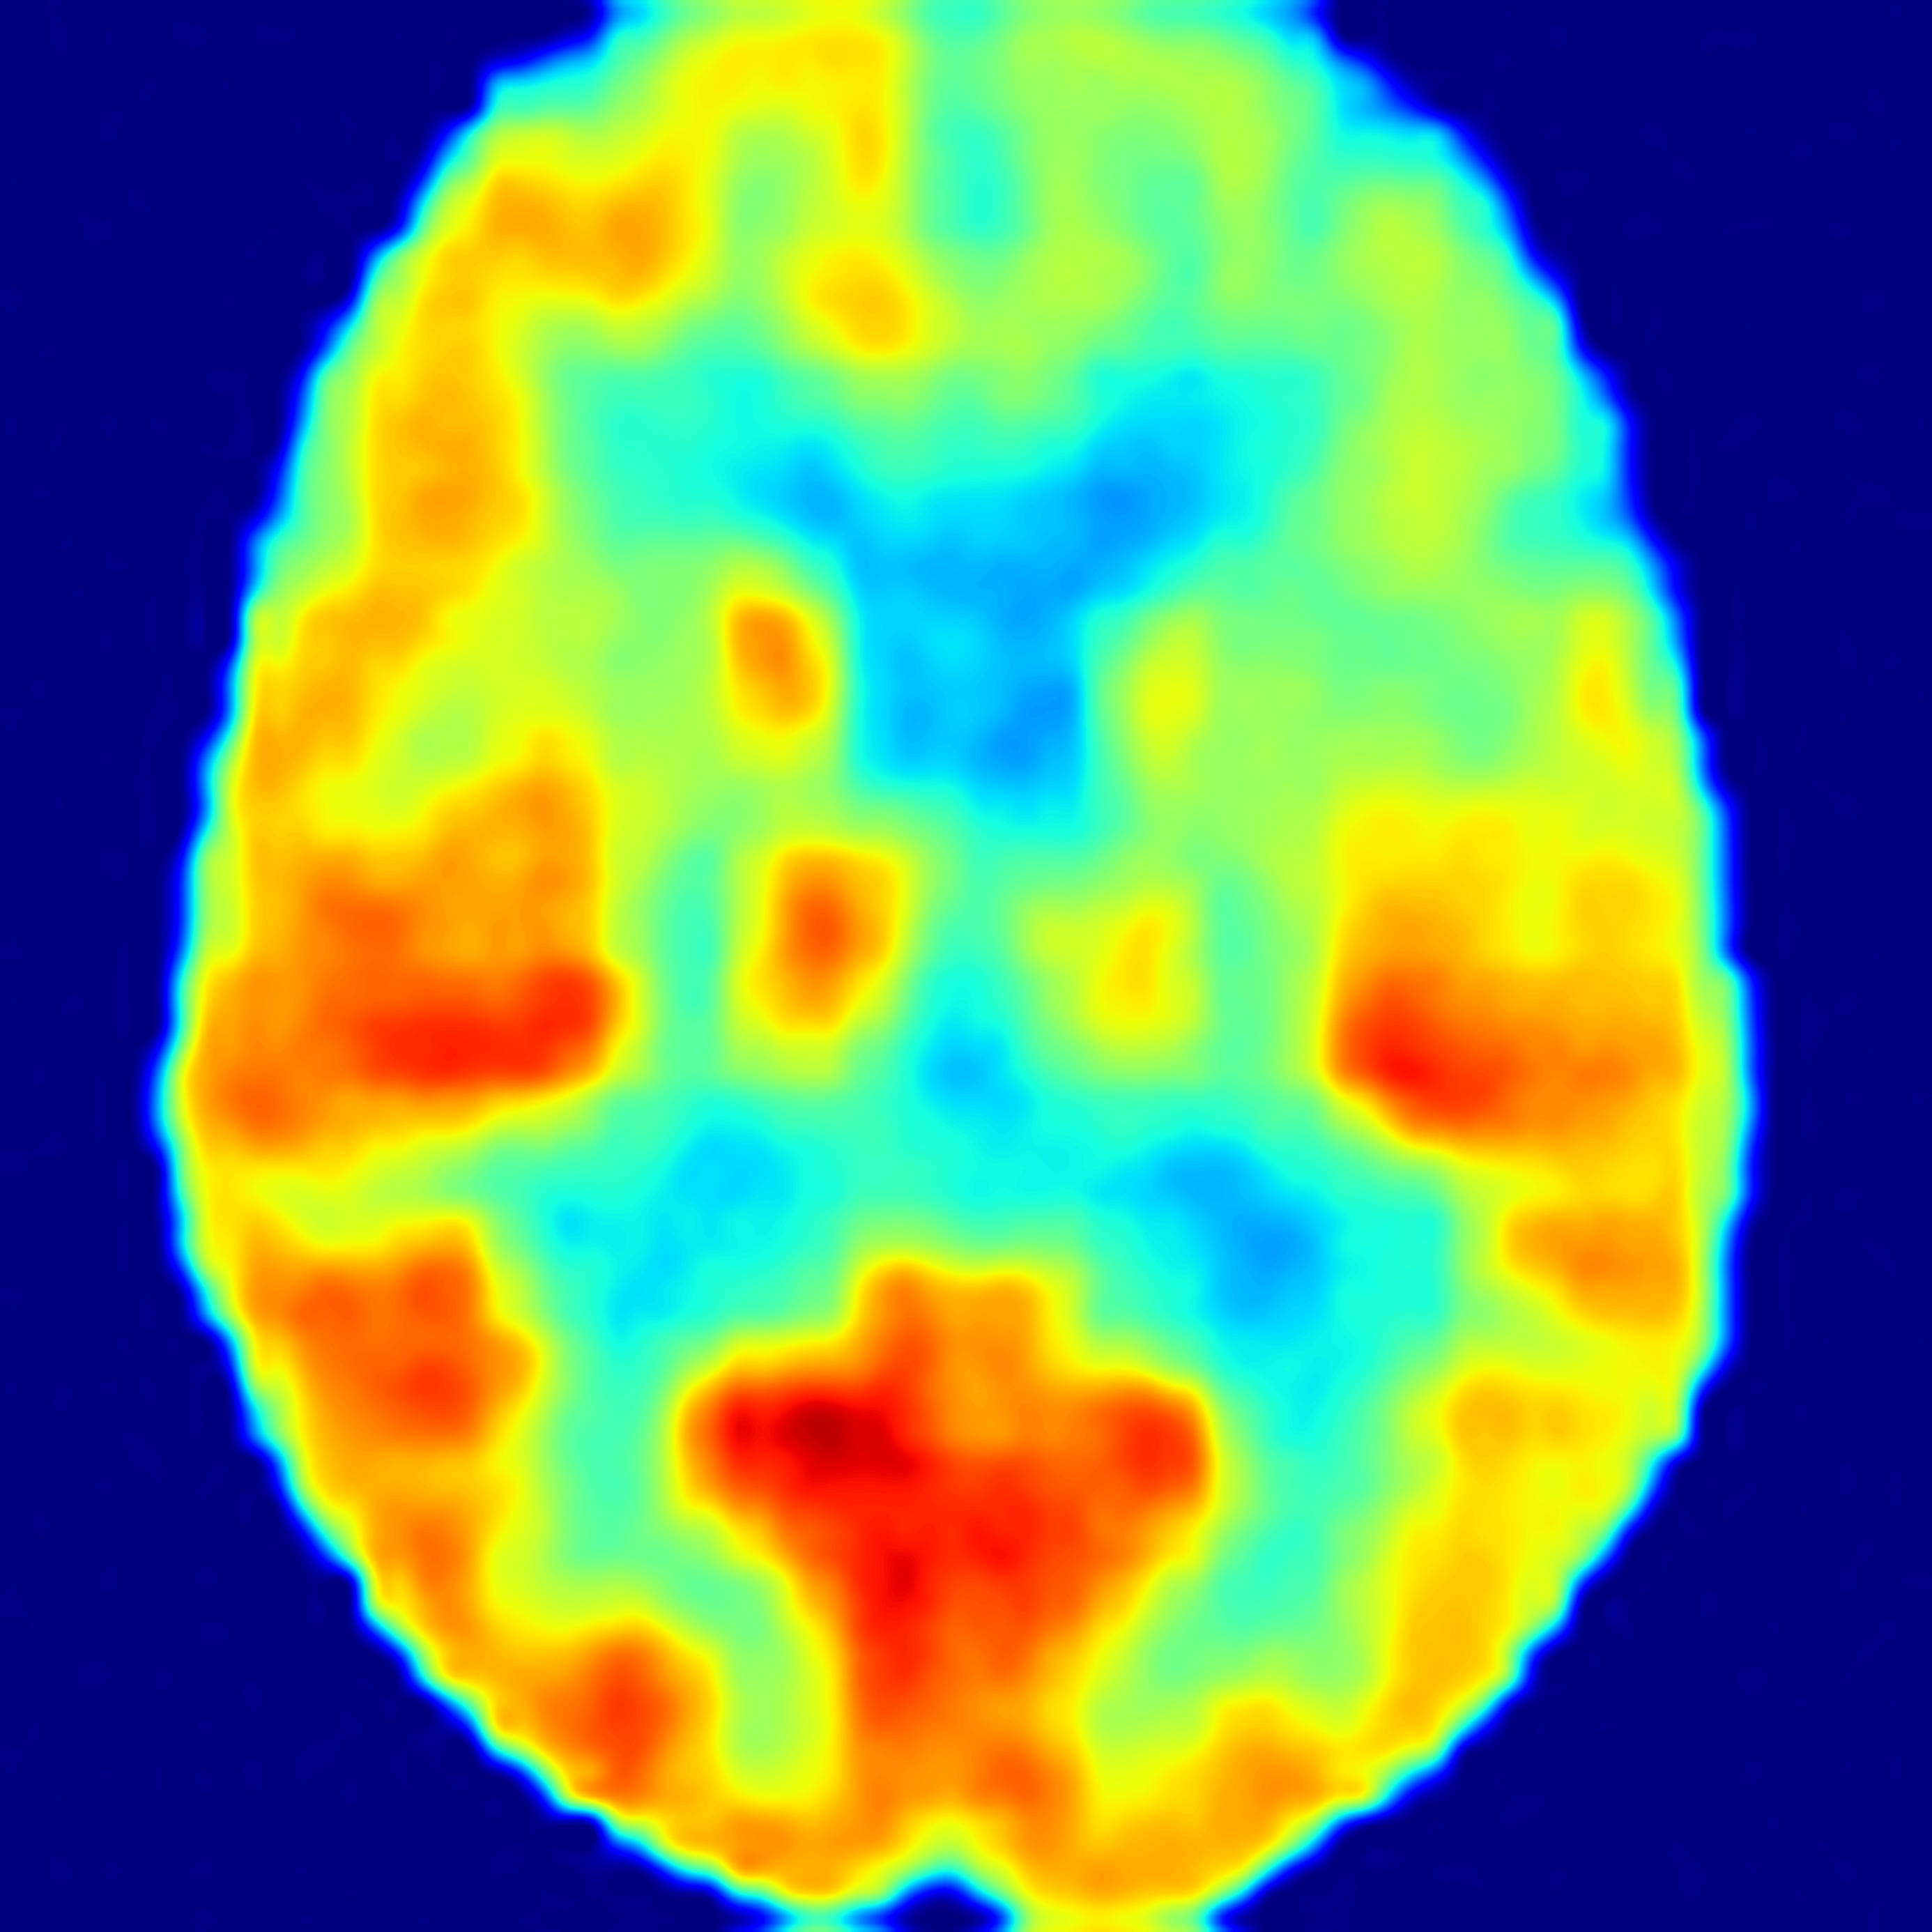

SiM2P simulates PET from MRI with high fidelity

(AD: Alzheimer's Disease, FTD: Frontotemporal Dementia, CN: Normal Control)

82 years old female with AD

66 years old female with AD

71 years old male with FTD

60 years old female with FTD

69 years old female as CN

70 years old male as CN

SiM2P employs a 3D diffusion bridge to simulate PET (SimPET) from structural MRI, conditioned on available auxiliary data. We validated the diagnostic utility of SimPET in a blinded clinical reader study, where SimPET showed significantly higher accuracy than MRI.

In a blinded clinical reader study, SimPET from SiM2P improved diagnostic accuracy by up to 12% over MRI across a range of tasks, with substantially increased interrater reliability.

SiM2P offers high pathological sensitivity even in scenarios where structural MRI lacks sufficient pathological atrophy, such as in early-stage or atypical presentations of AD.